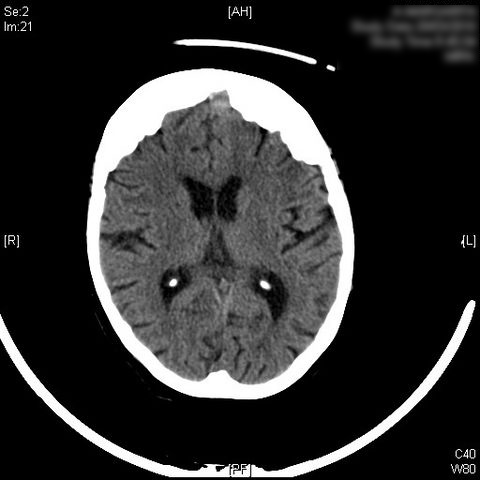

AVC amplio de territorio de A. cerebral media